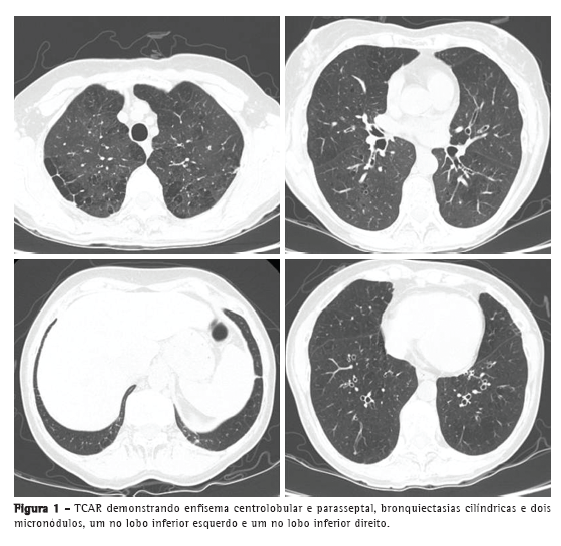

A TCAR demonstrou enfisema centrolobular e parasseptal, bronquiectasias cilíndricas, de predomínio central e nos lobos superiores, e dois micronódulos, com 3 e 4 mm de diâmetro, respectivamente, no lobo inferior direito e no esquerdo (Figura 1). A quantificação de imunoglobulinas revelou um aumento da IgE total (671 UI/mL), sem outras alterações. O doseamento de alfa-1 antitripsina foi normal. O estudo funcional respiratório revelou uma síndrome ventilatória obstrutiva, moderadamente grave, com insuflação, diminuição moderada da difusão alvéolo-capilar e leve insuficiência respiratória tipo 1. A resposta ao broncodilatador foi negativa (Tabela 1). O eletrocardiograma foi normal, e o estudo microbiológico do escarro foi negativo.